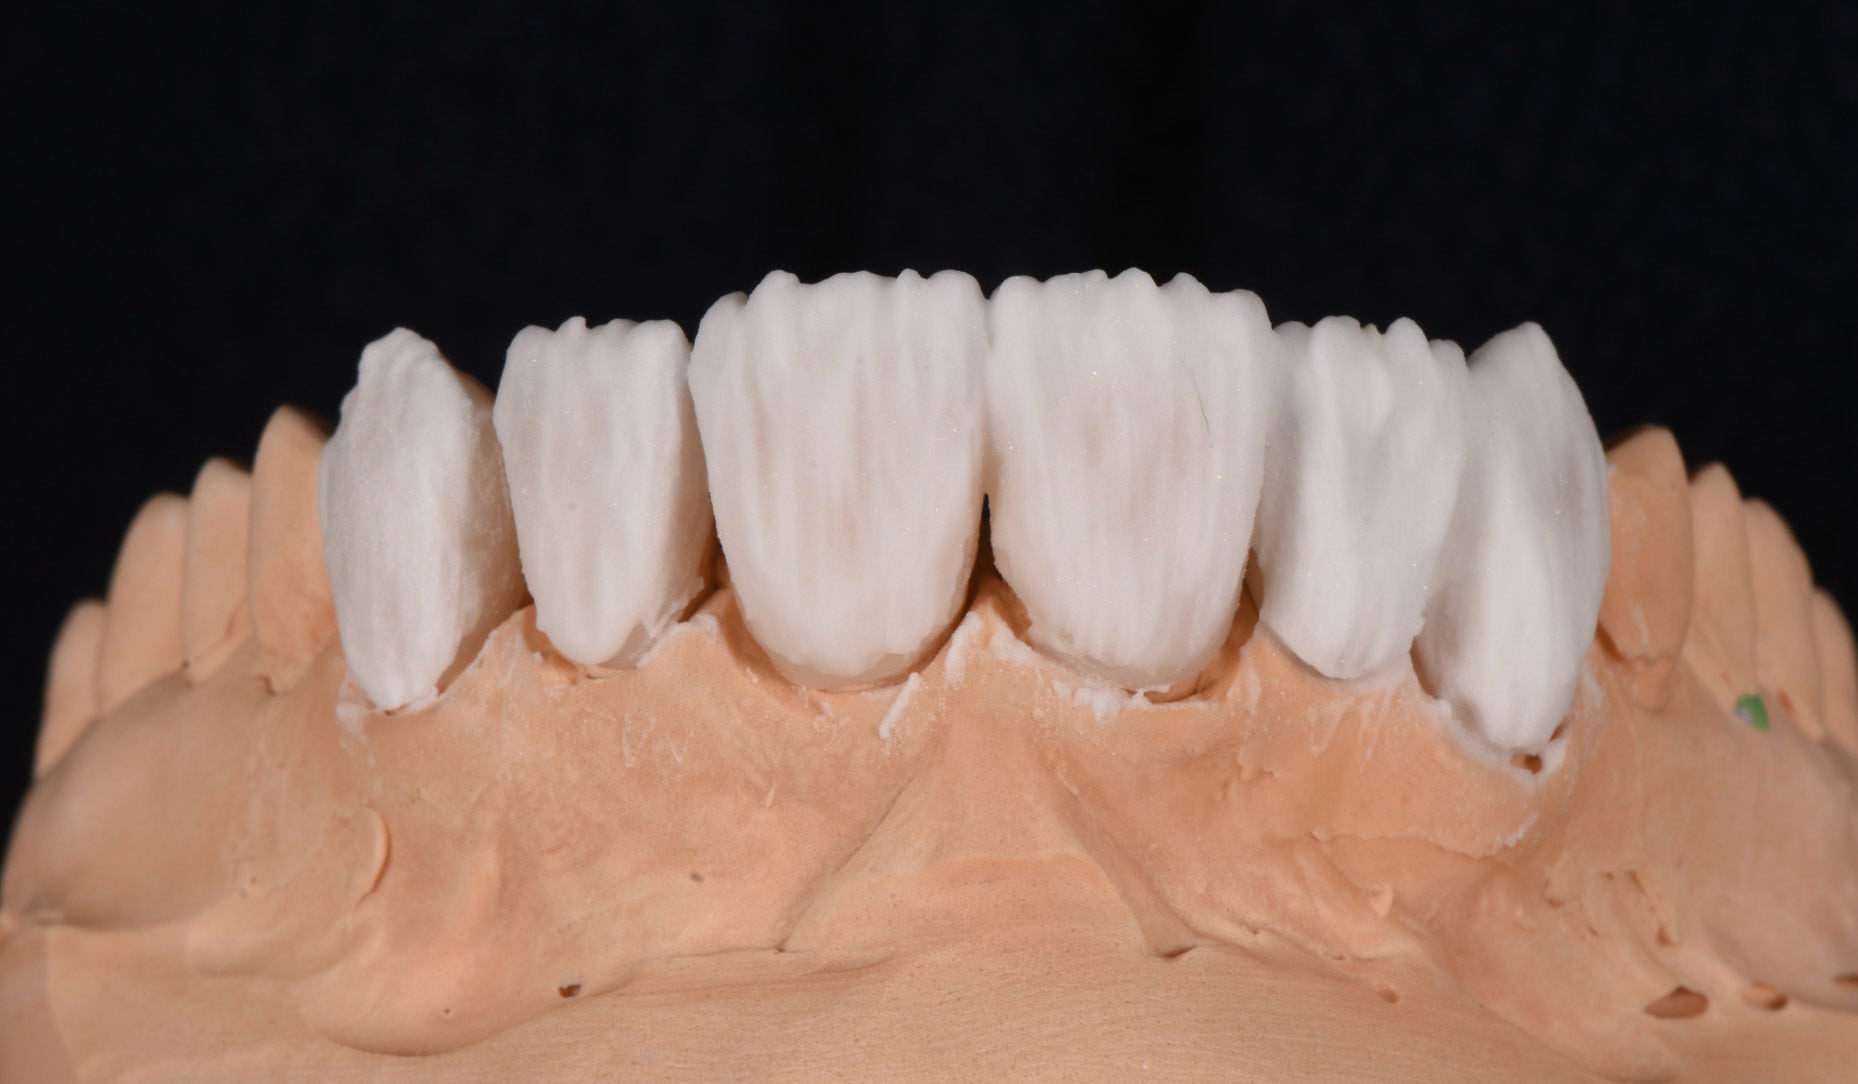

Clinical Cases, Labside Two high-strength ceramics, one micro-layering system Case by DT Andreas Chatzimpatzakis AESTHETIC AND EFFICIENT SMILE MAKEOVER Most patients asking for a smile makeover desire custom solutions rather than an off-the-peg smile: Individual tooth shapes that fit their face and their character, an internal play of colours that matches their age and natural dentition. Modern dental materials allow us to deliver what they demand in many situations – usually at a reasonable price. For a long time, however, we have been facing challenges when combining cosmetic and medically indicated treatment – e.g. a smile makeover including the rehabilitation of a missing lateral incisor. A straightforward solution – using lithium disilicate veneers alongside a zirconia cantilever bridge, both finished with their respective porcelain systems – would have been complicated by potential differences in the final appearance. With CERABIEN™ MiLai (Kuraray Noritake Dental Inc.), a set of internal stains and porcelains designed for micro-layering, the situation is different: Suitable for micro-layering on zirconia and lithium disilicate, it supports its user ideally in creating a harmonious smile even when the two framework materials are combined. A NEW CUSTOM SMILE The following patient case is a perfect example: A female patient with a missing lateral incisor, multiple visible composite restorations in the anterior region and an enamel fracture at her incisal edge desired a smile makeover. The selected materials were Amber Press LT (HASS), shade A1, for four veneers on the central incisors and the left lateral incisor and canine (teeth # 11, 21, 22 and 23 according to the FDI notation) and KATANA™ Zirconia YML (Kuraray Noritake Dental Inc.), shade A2, for the planned cantilever bridge on the maxillary right canine, replacing the missing lateral incisor (teeth # 12 and 13). Fig. 1. Female patient with a missing maxillary lateral incisor and multiple composite restorations in the anterior area – a smile makeover is desired. Fig. 2. Patient with mock-up. Fig. 3. Minimally invasive preparation through the mock-up, which takes into account the minimum space required for the planned materials and restorations. Fig. 4. Teeth prepared for the all-ceramic restorations. Fig. 5. Occlusal view of the maxillary teeth after tooth preparation. Fig. 6. Full-contour veneers and cantilever bridge on the model. Fig. 7. Restorations after a cutback limited to the vestibular and incisal area. Fig. 8. CERABIEN™ MiLai LT1 is applied to the middle and cervical area of the zirconia cantilever bridge. Fig. 9. CERABIEN™ MiLai Value Liner 2... Fig. 10. … and Value Liner 1 applied to the incisal area of the central and lateral incisor restorations. Fig. 11. CERABIEN™ MiLai porcelain Creamy Enamel mixed with Value Liner 2 (70/30) added to the middle and cervical areas of the four lithium disilicate restorations to increase and control the value. Fig. 12. ... while E2 is added to the incisal area of both canines. Fig. 13. Restorations covered by a layer of Tx ... Fig. 14. ... and LTx. Fig. 15. Appearance of the restorations after the first bake. Fig. 16. Adding translucency and opalescence to the cervical area with LT1 and brightness to the ridges with Creamy Enamel. Fig. 17. Completion of the enamel surface with a cover layer of LTx, which is responsible for a high translucency and opalescence. Fig. 18. Result of the second bake. Fig. 19. Final restorations with a natural self-glaze effect on the model. Fig. 20. Final restorations with a natural self-glaze effect in the patient’s mouth. Fig. 21. Smooth optical integration of the restorations. Fig. 22. Beautiful treatment outcome. CONCLUSION With the described approach and selected materials, it was possible to create restorations with a natural shade, shape and texture. They matched not only the appearance of the remaining natural teeth, but also showed internal consistency across the selected framework materials. The technical procedure was quite straightforward and efficient, while the result speaks for itself. Special thanks to Dr. Kanellos Ioannis for the collaboration on this case and for kindly providing the pre- and post-treatment photographs that complemented it. Dental technician: ANDREAS CHATZIMPATZAKIS Based in Athens, Greece, Andreas Chatzimpatzakis is the founder and director of ACH Dental Laboratory (since 2000), specializing in refractory veneers, lithium disilicate, zirconia, and implant prostheses. He graduated in Dental Technology from the University of West Attica and received advanced training in all-ceramic restorations in Helsinki and Japan under renowned masters including Shigeo Kataoka. Since 2017, he has served as an international trainer for Kuraray–Noritake Dental Inc., delivering lectures and hands-on courses worldwide on advanced ceramic techniques. He has also held roles as Key Opinion Leader for MPF Brush Co., Ambassador for Hass Co., and Editor-in-Chief of Laborama. An active member of the Hellenic Academy of Aesthetic Dentistry, his work and articles have been published in both Greek and international journals. Jan 21, 2026 Dental Technician Kuraray Noritake Prosthodontics Clinical Case Katana Zirconia YML CERABIEN MiLai Prosthetic dentistry Lab Dental Ceramics Cad Cam Discs KATANA Zirconia YML View Product CERABIEN MiLai View Product Subscribe to our Newsletter Join thousands of dental professionals and receive free advice that can help you and your career. We will not spam or share your e-mail.